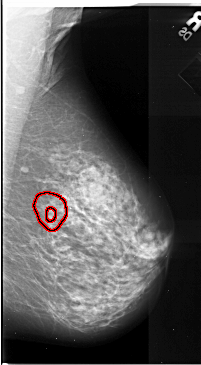

A_1087_1.LEFT_MLO

LEFT_MLO LINES 6691 PIXELS_PER_LINE 3706 BITS_PER_PIXEL 16 RESOLUTION 42 NON_OVERLAY

FILE: A_1087_1.RIGHT_MLO.OVERLAY

TOTAL_ABNORMALITIES 1

ABNORMALITY 1

LESION_TYPE MASS SHAPE ARCHITECTURAL_DISTORTION MARGINS SPICULATED

ASSESSMENT 5

SUBTLETY 1

PATHOLOGY MALIGNANT

TOTAL_OUTLINES 2

BOUNDARY

CORE